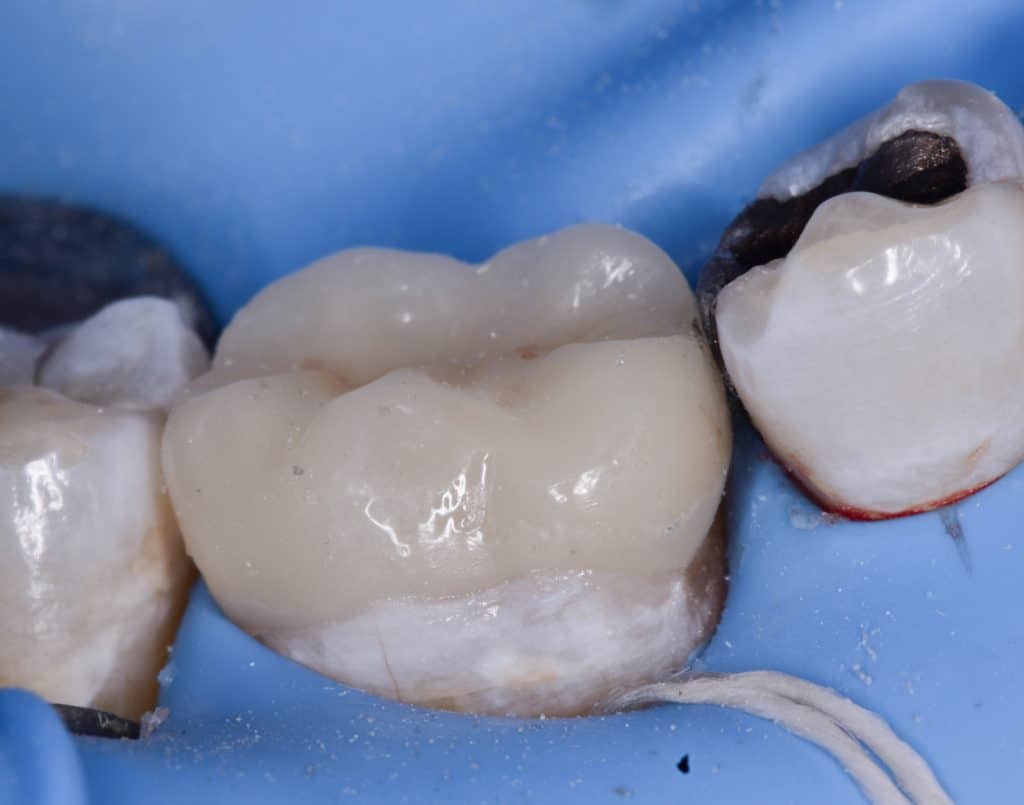

During amalgam removal

Old amalgam and screw removed